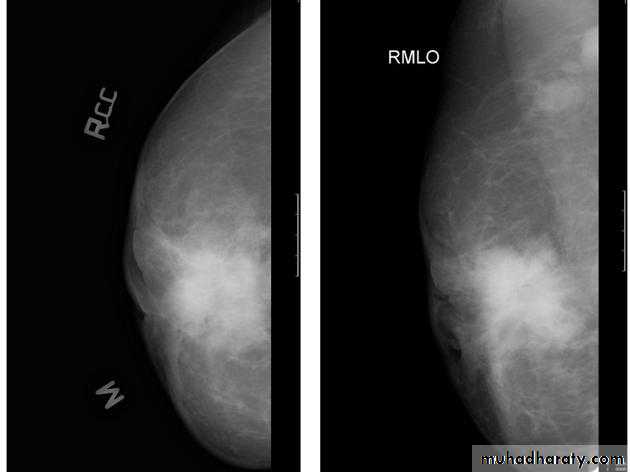

The mediolateral oblique (MLO) view is one of standard mammographic views. It is the most important projection as it allows to depict most breast tissue.

The craniocaudal view (CC view), is one of the two standard projections in a screening mammography. It must show the medial part as well the external lateral portion of the breast as much as possible.